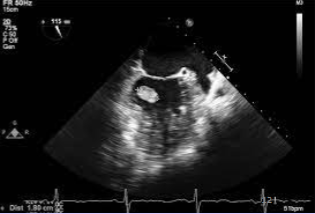

Myxoma

<p>Most common adult primary benign tumor.</p><p>75% occur in the right atrium.</p><p>Most often arise from the fossa ovalis.</p><p>Mobile, lobular mass.</p>

Fossa ovalis of the IVS

Myxomas most often arise from the ____.

Irregular shape with protruding “fronds” of tissue or grape cluster.

Heterogenous - areas of necrosis and hemorrhage.

Usually solitary; multiple if from familial syndromes.

May become quite large and cause hemodynamic obstruction.